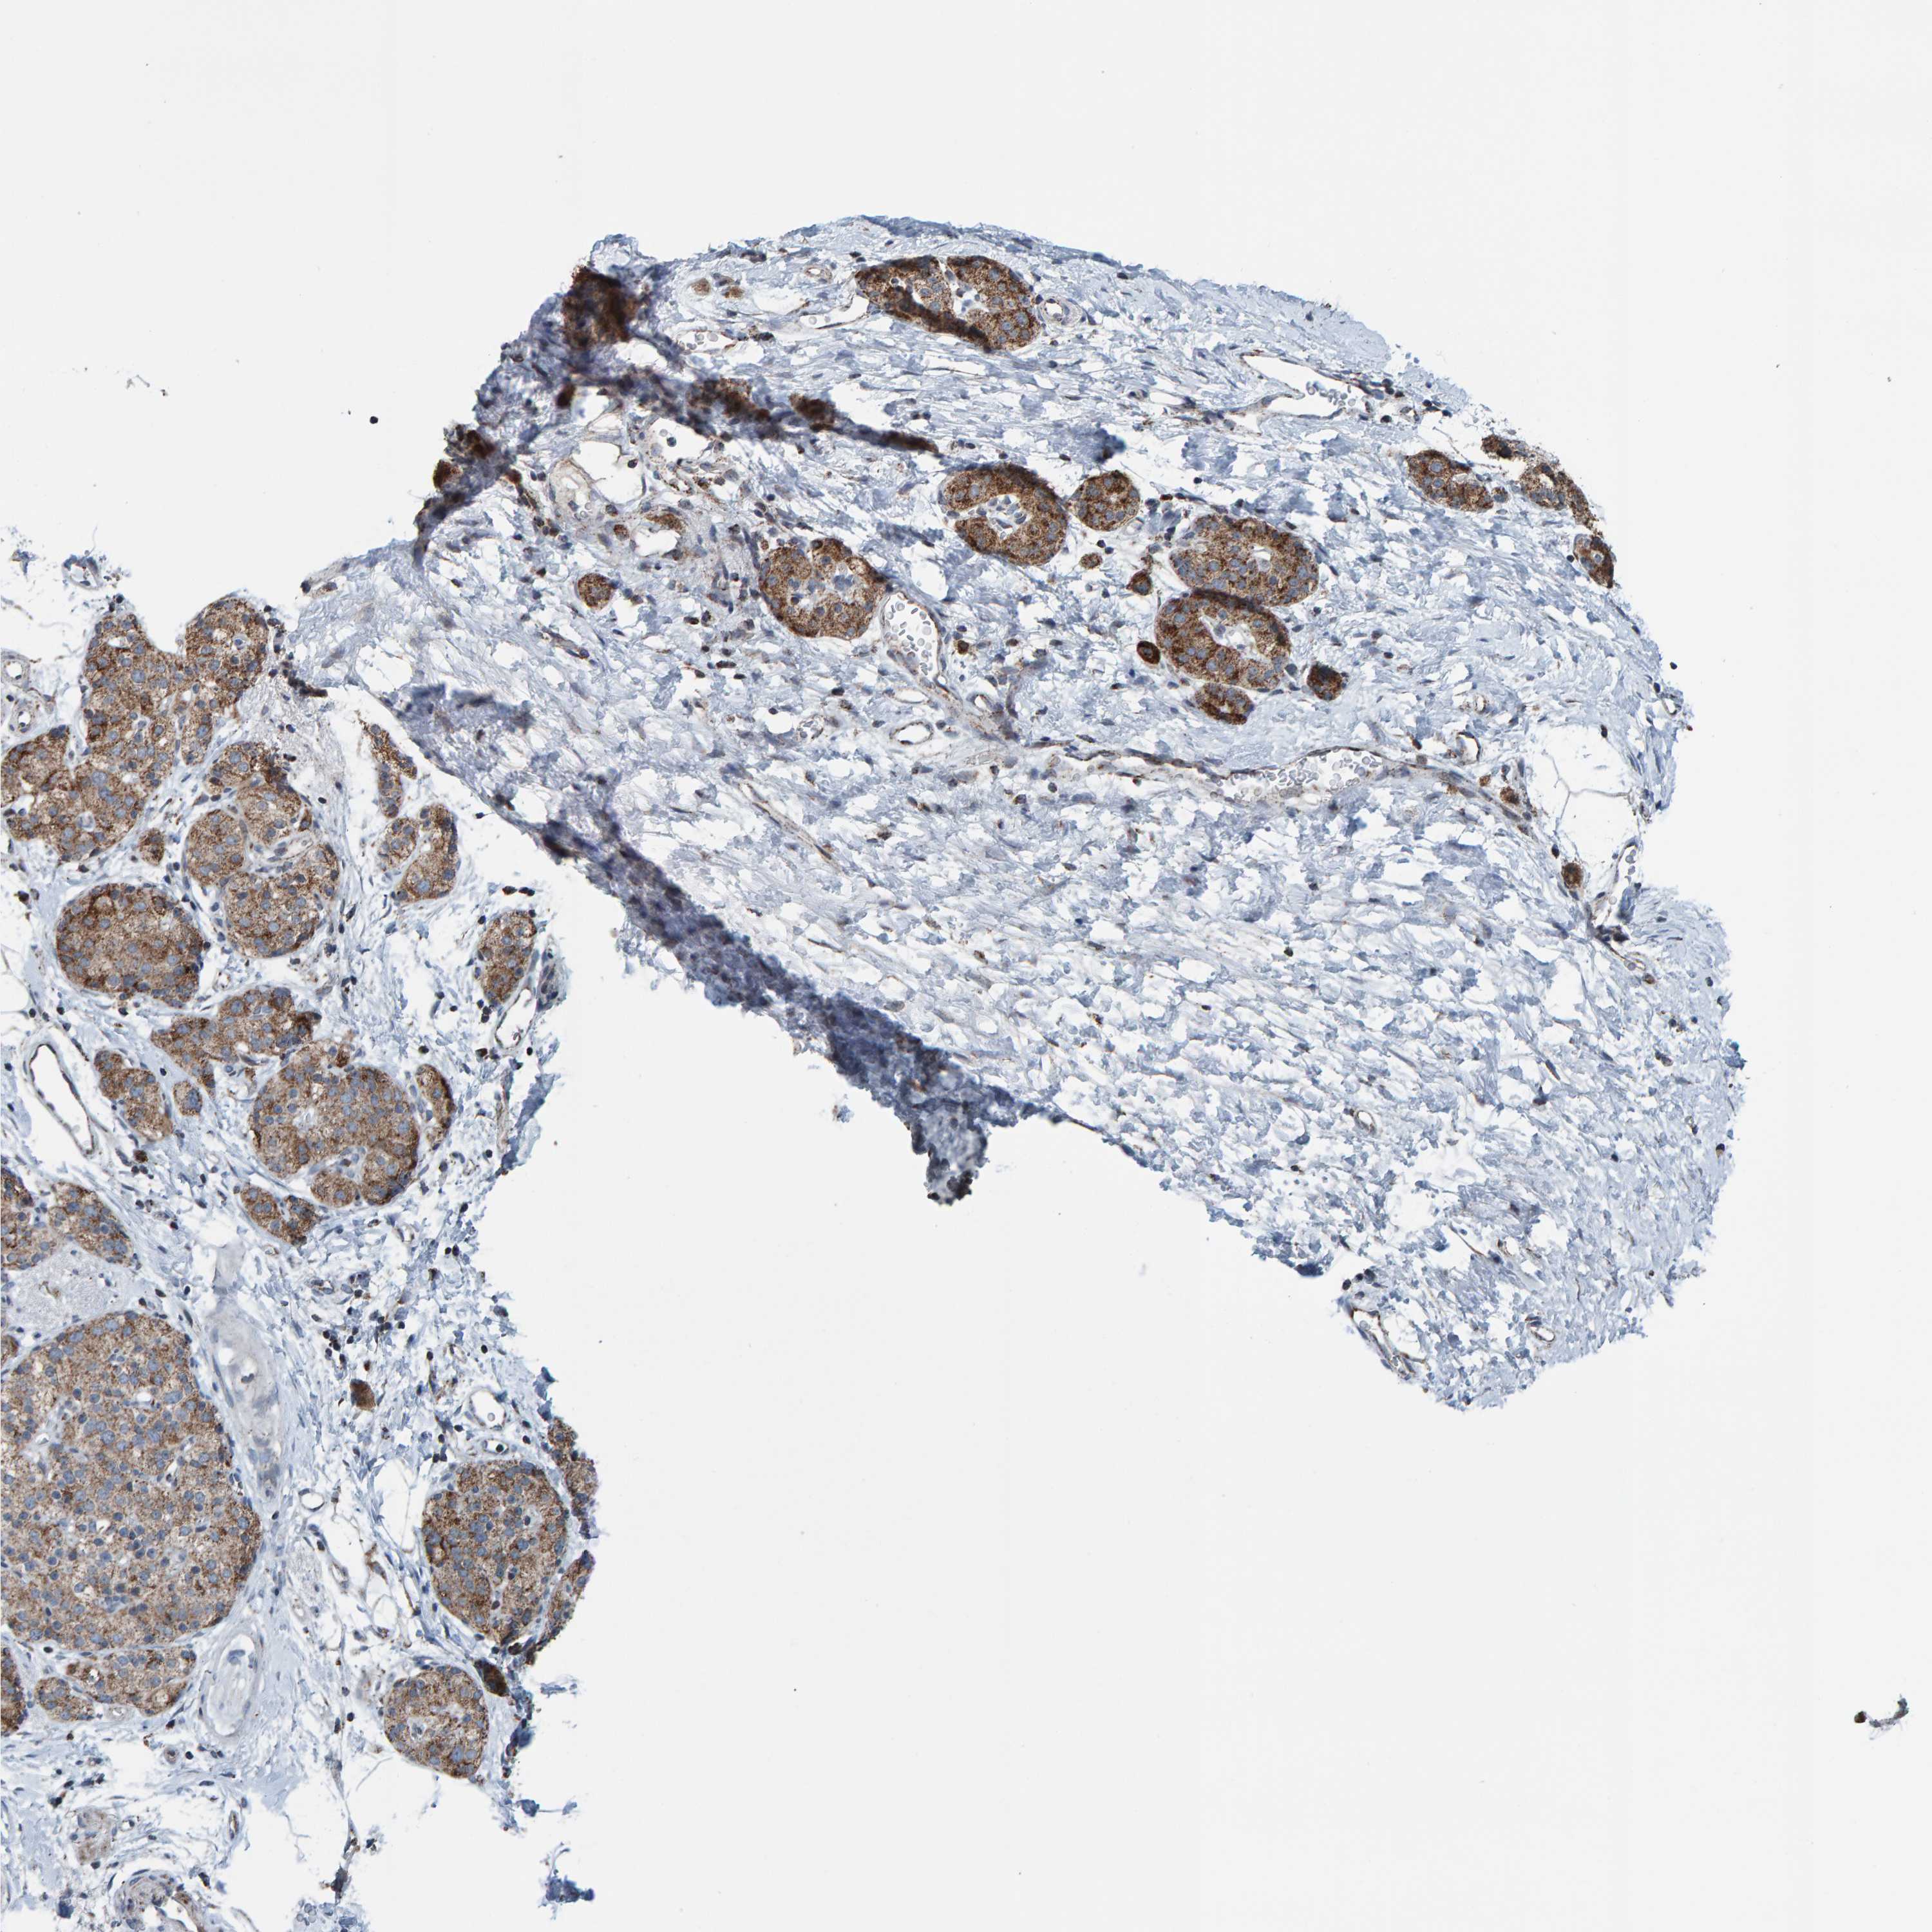

PANCREATIC CANCER - Protein expressioni

A mouse-over function shows sample information and annotation data. Click on an image to view it in a full screen mode. Samples can be filtered based on level of antibody staining by selecting one or several of the following categories: high, medium, low and not detected. The assay and annotation is described here.

Note that samples used for immunohistochemistry by the Human Protein Atlas do not correspond to samples in the TCGA dataset.

Antibody stainingi

Antibody staining in the annotated cell types in the current human tissue is reported as not detected, low, medium, or high, based on conventional immunohistochemistry profiling in selected tissues. This score is based on the combination of the staining intensity and fraction of stained cells.

Each image is clickable and will lead to virtual microscopy that enables deeper exploration of all samples and also displays staining intensity scores, fraction scores and subcellular localization as well as patient and tissue information for each sample.

Antibody HPA023806

Staining

High

Medium

Low

Not detected

Intensity

Strong

Moderate

Weak

Negative

Quantity

>75%

75%-25%

<25%

None

Location

Nuclear

Cytoplasmic/membranous

Cytoplasmic/membranous,nuclear

Adenocarcinoma, NOS